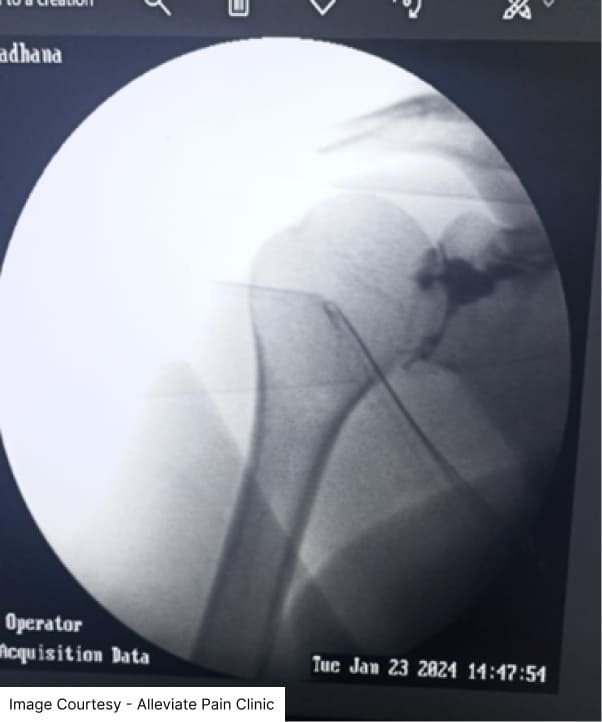

Shoulder Intrarticular stem cell and platelet rich plasma injection done under fluoroscopic guidance at Alleviate Pain Clinic